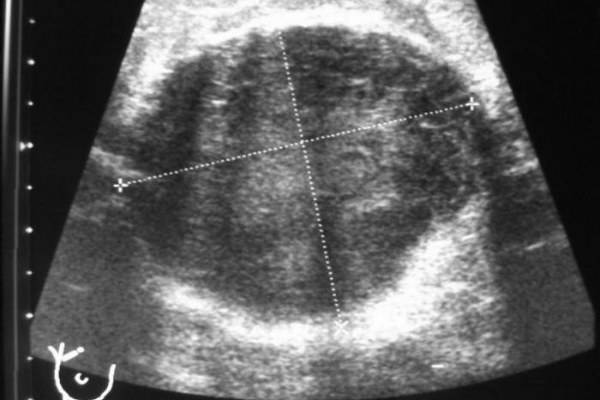

Мастит. Присутствуют очаговые образования вблизи от ареолярного сегмента. Контуры ровные, структура однородная с незначительными усилениями. Рисунок выглядит затушеванным. На нем четко различимы гомогенные зоны с участками воспаления. При наличии гнойных очагов расширяются альвеолы и протоки, которые окружены инфильтратом, имеющим вид сот.

Киста. На УЗИ видны хорошо различимые образования с гладкими и четкими стенками. Внутри имеется жидкое содержимое (темный цвет). Киста сжимается под действием аппарата.

Для проведения дифференциальной диагностики с маститом таким женщинам рекомендовано прохождение УЗИ грудных желез. Обычно врачи-сонологи описывают расширение протоков, наличие в них большого количества секрета, усиление кровотока.

Основная цель ультразвукового исследования в маммологии – диагностика жидкостных и акустических плотных образований в груди, а также видимый контроль за лечебными и инвазивными манипуляциями. УЗИ диагностика является эффективным способом определить лактостаз. Сканограммы отражают застой в виде чрезмерно расширенных протоков молочной железы. Особенно четко можно увидеть расширение отдаленных протоков и синусов. При лактостазе, в отличие от мастита, наблюдается сохранение структуры молочной железы при отсутствии примесей крови и лимфы в тканях.